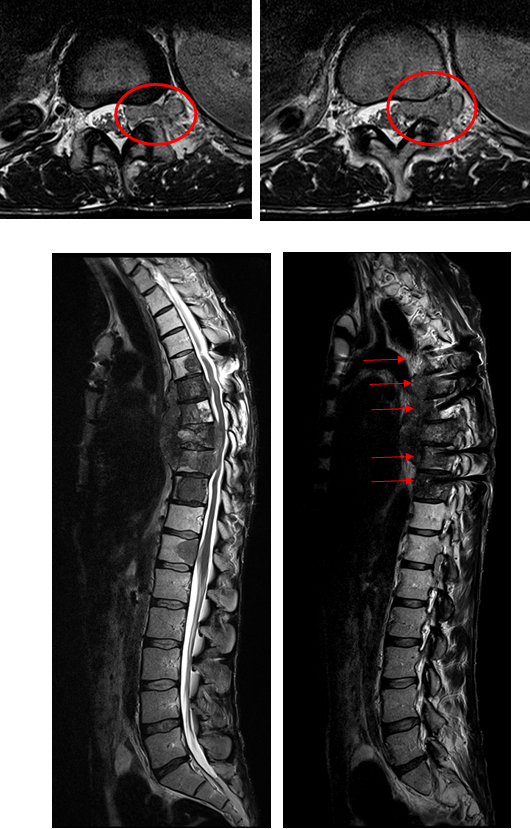

西门子MAGNETOMAera 1.5T纪元四度磁共振可进行神经系统、脊柱、四肢关节、腹部、心脏、血管等全身各个系统的不同疾病的检查,而且能进行波谱分析,对肿瘤的性质鉴定有很高临床价值。对CT无法发现的超早期脑梗塞病变具有无可替代的作用,能发现发病后几分钟内的病灶,为挽救患者生命和改善预后、减少致残率赢得时间,必将进一步提升诊疗水平,为临床诊断提供更有力的硬件支持,为广大患者带来福音。